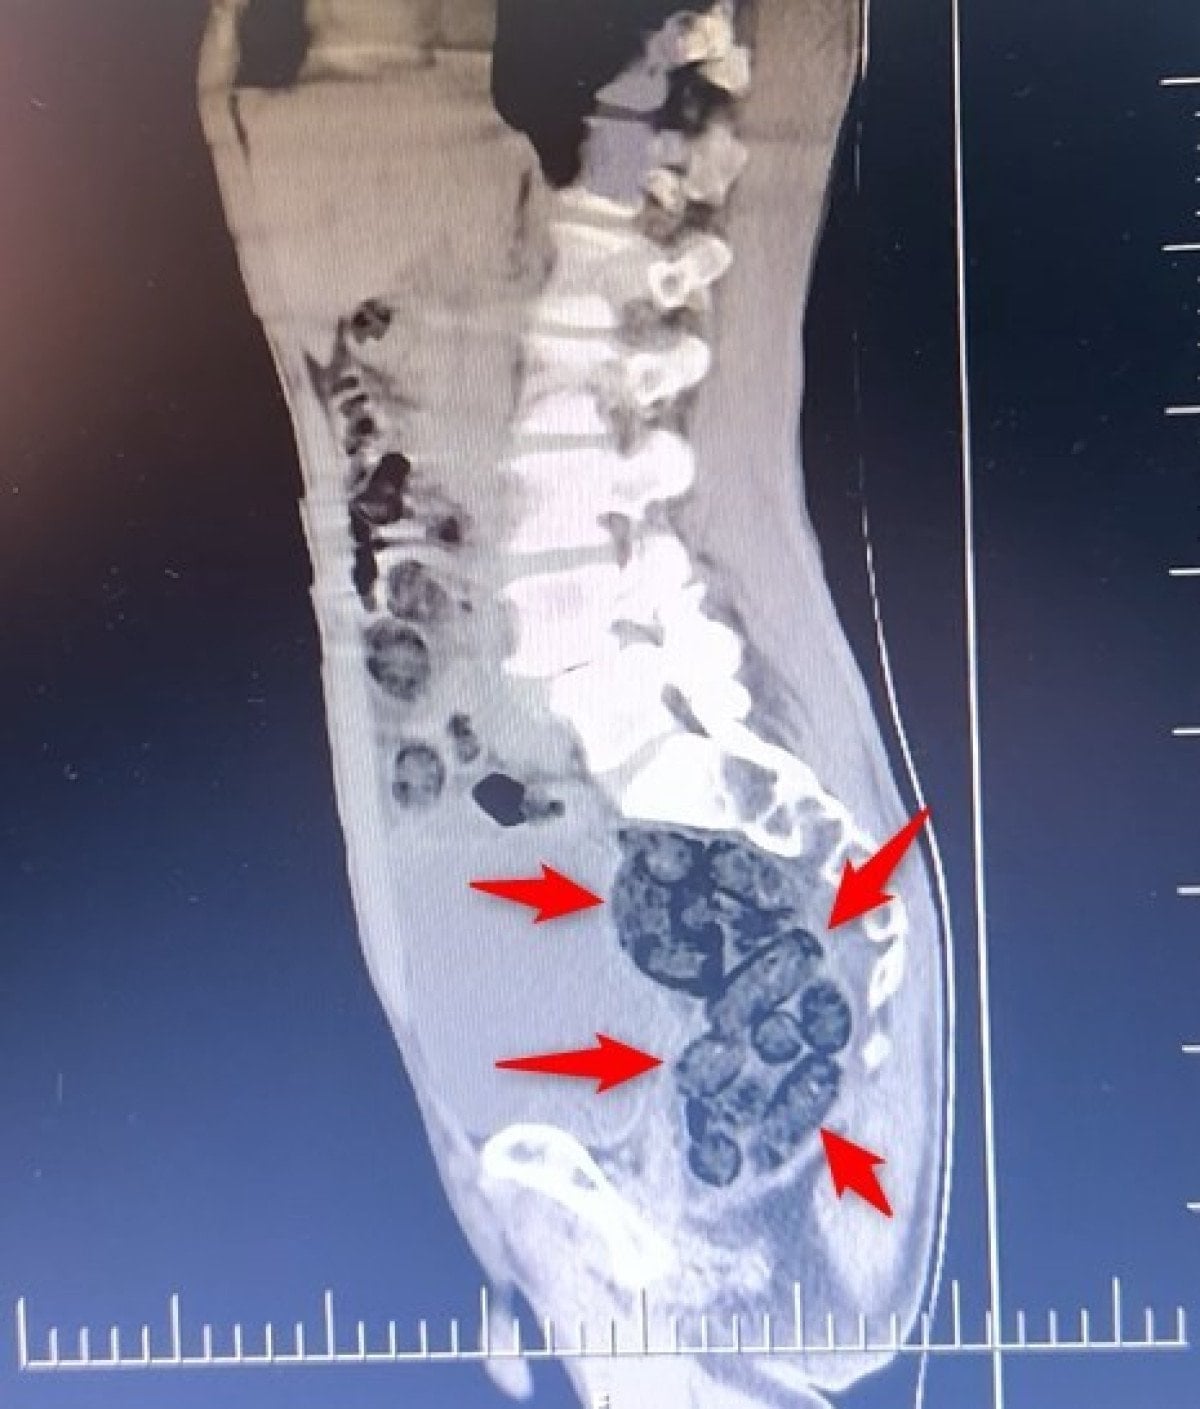

Yapılan incelemeler sonucunda yabancı uyruklu şahsın midesinde 64 parça halinde toplam 472 gram uyuşturucu maddesi metamfetamin olduğu belirlendi.

Gözaltına alınan şahsın midesindeki uyuşturucu madde çıkartıldı.